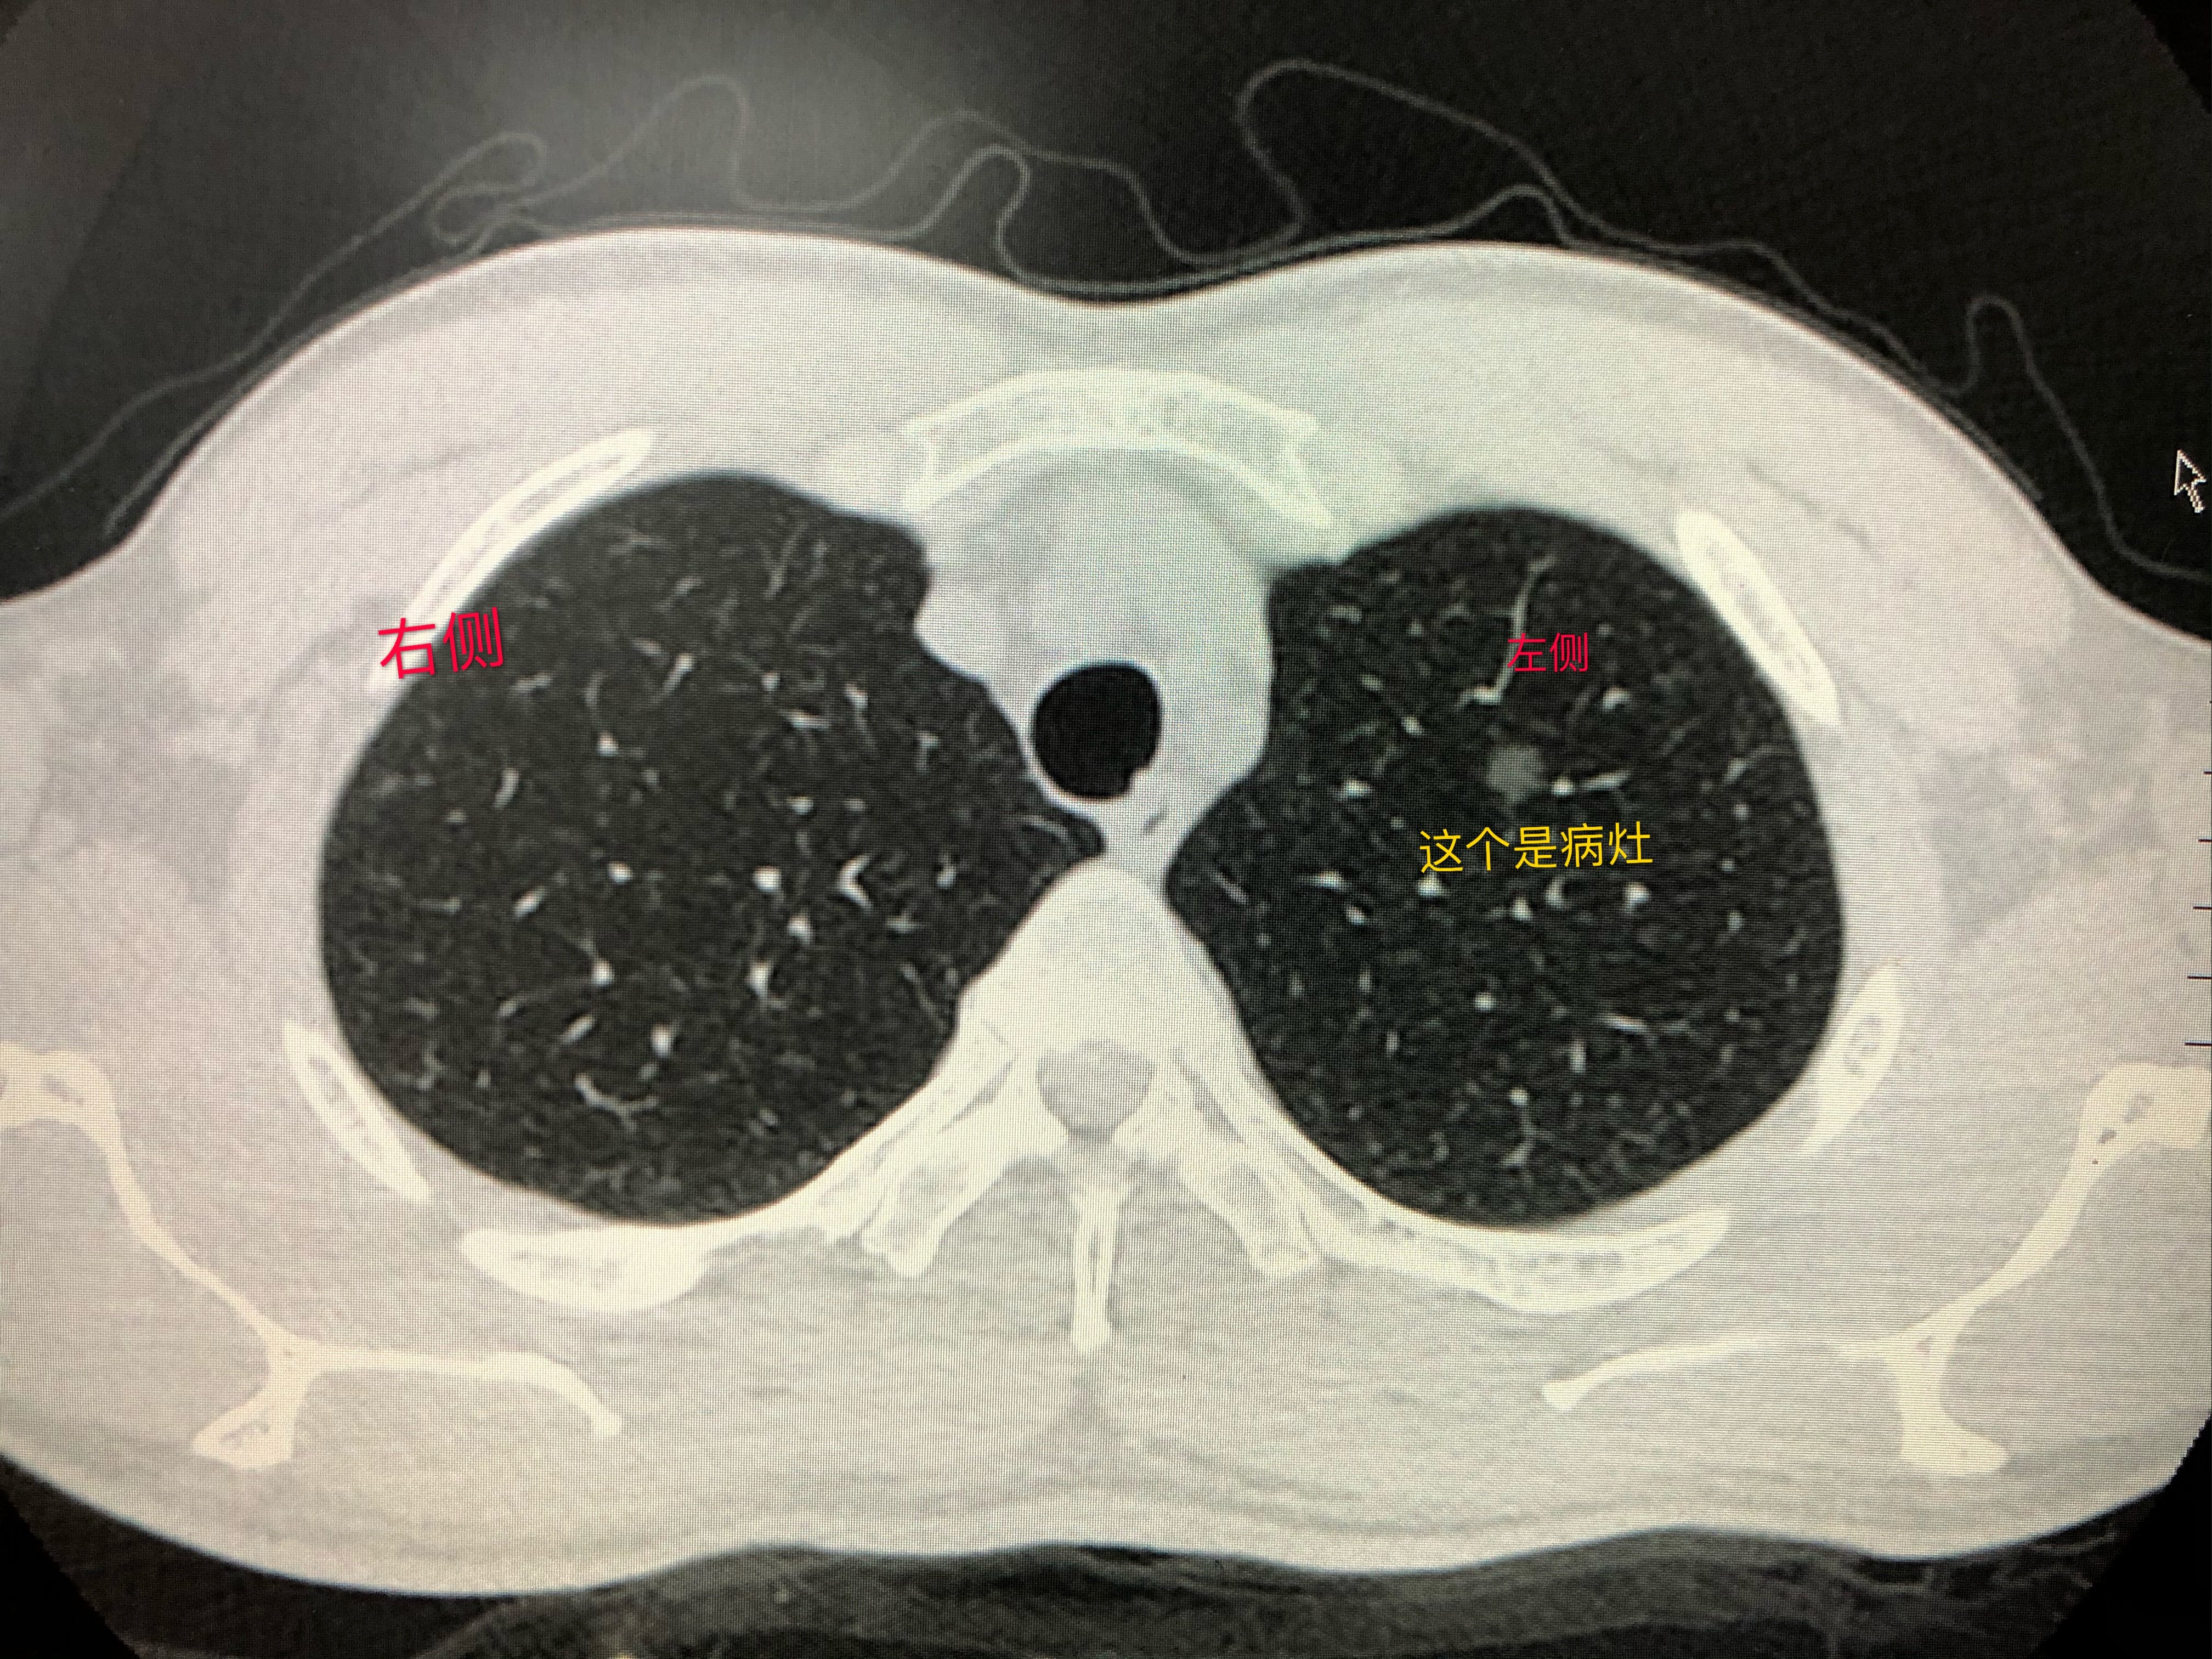

判断肺结节性质的“金标准”是通过手术将结节切除后进行病理学检查。有经验的医生可以通过影像学对肺磨玻璃结节的性质进行初步判断。根据胸部 CT 影像,肺磨玻璃结节可分为无实性成分的纯磨玻璃结节(图3-1)和包含实性成分的混合型磨玻璃结节(图 3-2)。评判肺磨玻璃结节的“好坏”,有客观标准。美国放射学会提出肺结节影像学Lung-RADS分级系统,以下是关于磨玻璃结节的部分: